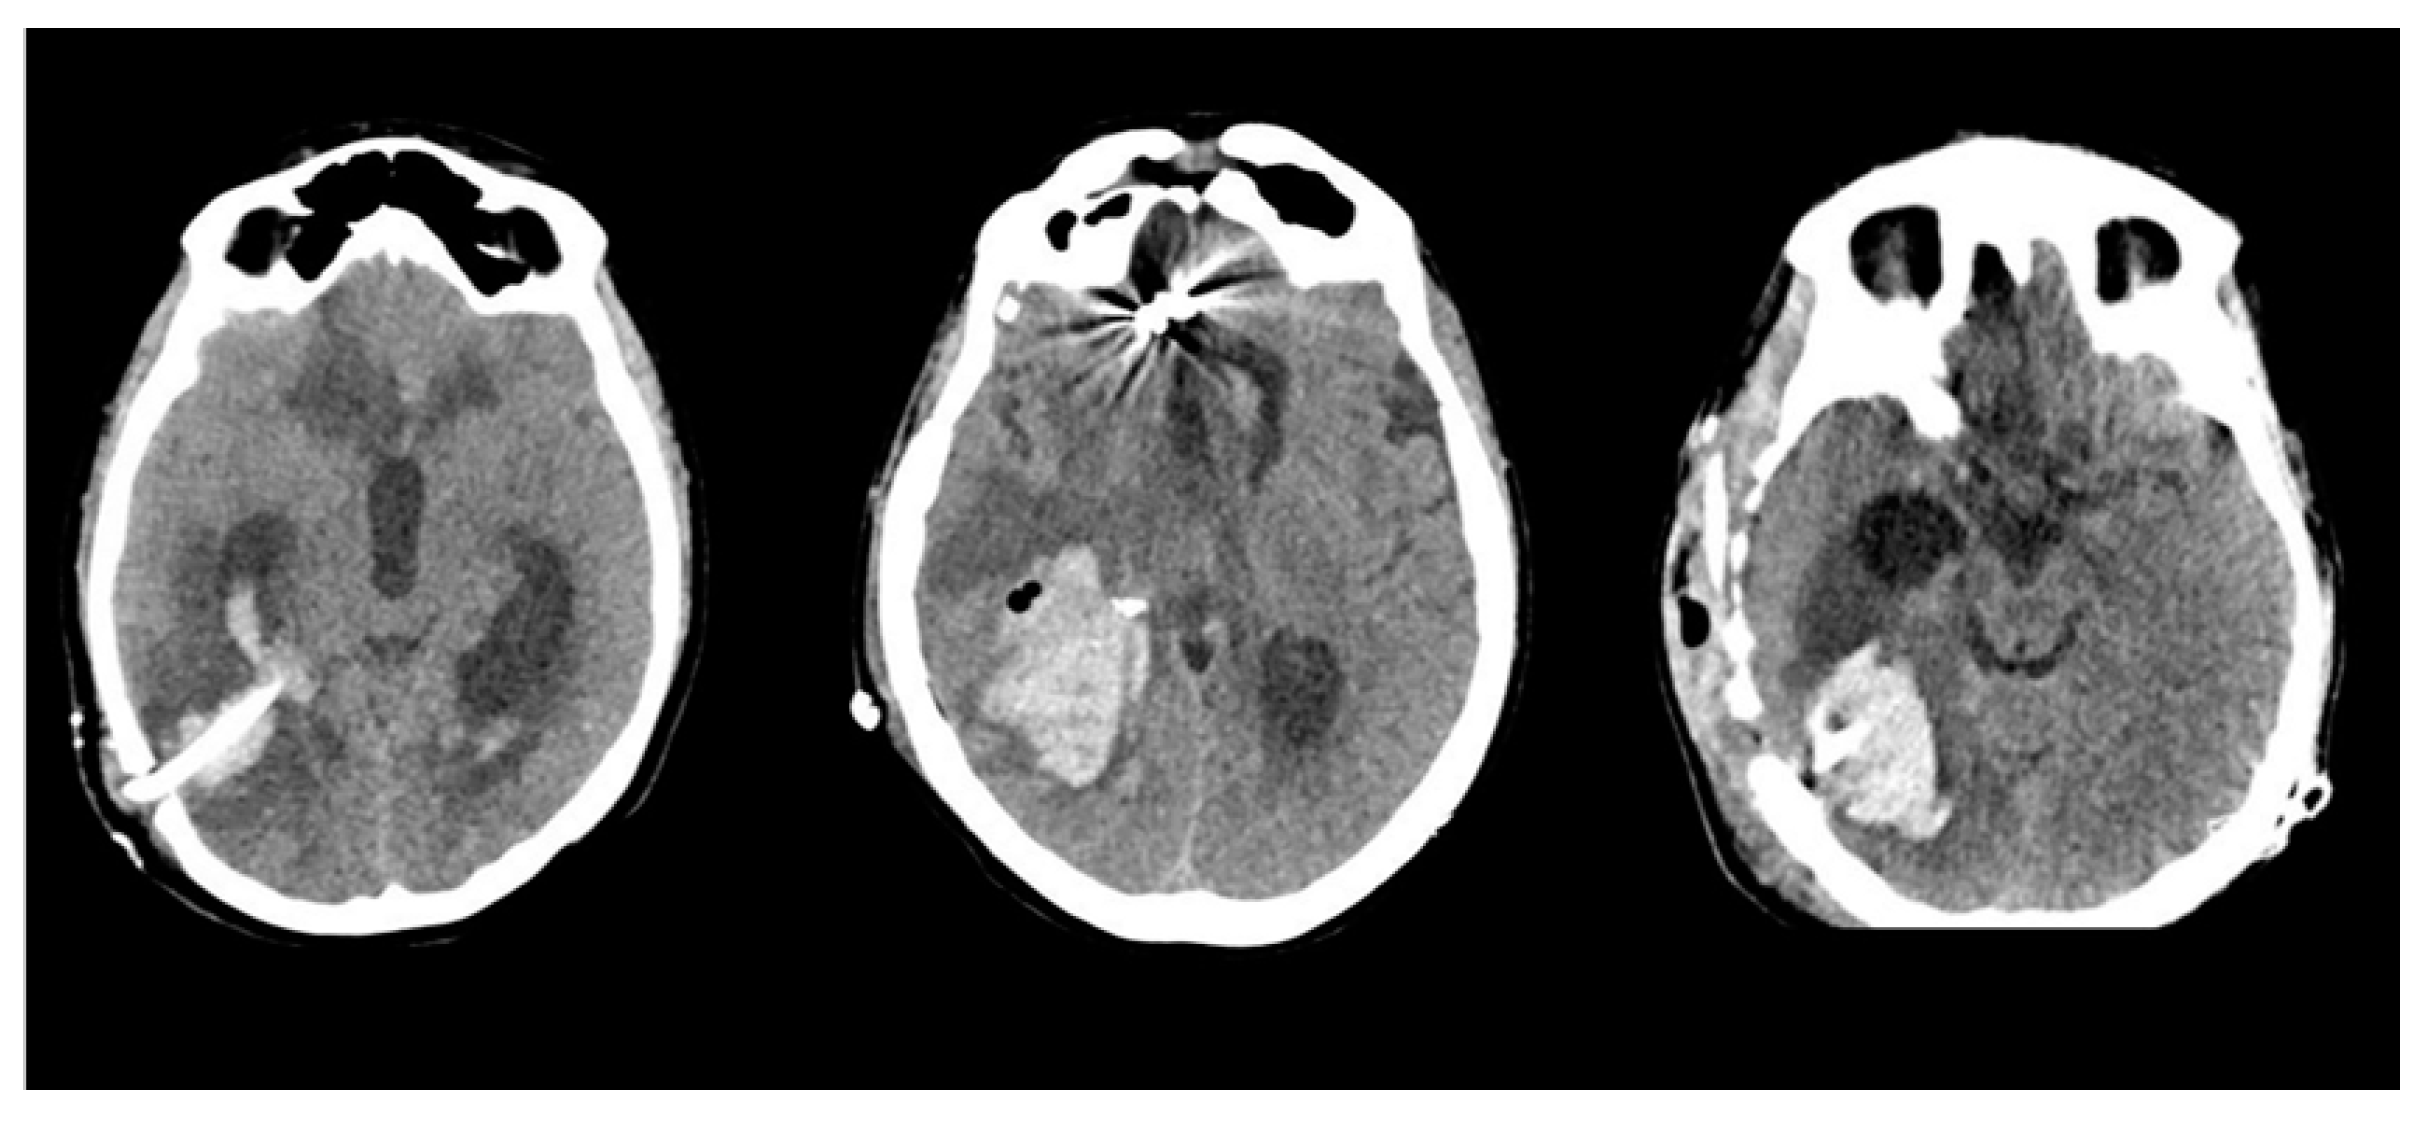

- The location of the hematoma was consistently distant from the arteriovenous malformation (AVM) nidus, surrounding the trajectory of the ventricular catheter.

- The occurrence of the hemorrhagic complication transpired several weeks after the initial AVM rupture and several days after the placement of the VPS.

- Catheter-related DICH manifested in all 10 cases without any evident coagulation disorders or other identifiable risk factors.